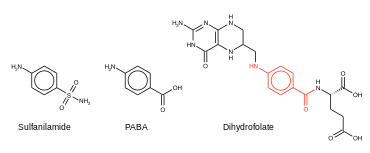

Plusieurs classes de composés antibiotiques ciblent différentes étapes de cette voie des folates :

Les sulfamidés et le sulfanilamide sont des analogues structurels de l'acide p-aminobenzoïque ou PABA. Ce dernier composé est l'un des éléments qui interviennent dans la synthèse des folates chez les bactéries et chez les plantes. Le sulfanilamide est un inhibiteur de la dihydroptéroate synthase et bloque la synthèse du dihydrofolate. Le triméthoprime intervient en aval dans la voie, en inhibant la synthèse de tétrahydrofolate par la dihydrofolate réductase. Le triméthoprime est sélectif de la dihyrdrofolate réducate des bactéries et n'inhibe pas l'enzyme humaine, ce qui rend possible son utilisation thérapeutique comme antibiotique (contrairement au méthotrexate, qui inhibe la dihydrofolate réductase humaine et est utilisé comme anticancéreux)